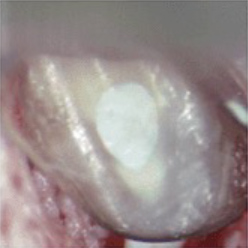

- ⑥ 逆根管充填後の歯根端の断面です。歯根が乾燥しないうちに速やかに再植します。